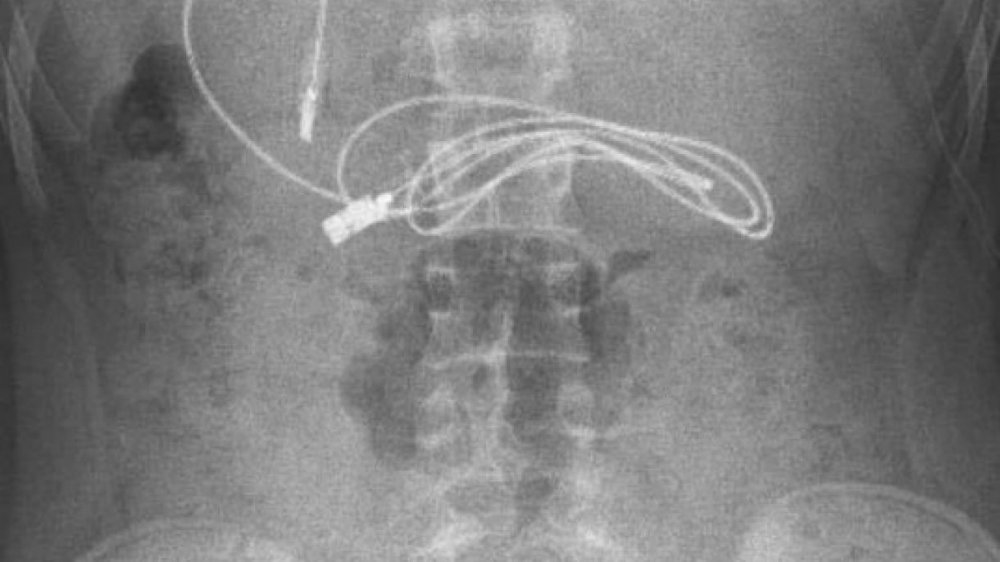

Diyarbakır'da kusma ve bulantı şikayetiyle hastaneye götürülen, çekilen röntgeninde 1 metrelik şarj kablosu ve toka yuttuğu tespit edilen 15 yaşındaki erkek çocuğu, Elazığ'da gerçekleştirilen operasyonla yuttuğu cisimlerden kurtuldu.

Diyarbakır'da kusma ve bulantı şikayetiyle ailesi tarafından hastaneye götürülen erkek çocuğunun çekilen röntgeninde, midesinde şarj kablosu ve toka olduğu tespit edildi. Bunun üzerine çocuk, ambulans ile Fırat Üniversitesi Hastanesi'ne sevk edildi.

Ameliyatı gerçekleştiren Prof. Dr. Yaşar Doğan, kablonun bir ucunun ince bağırsağa geçmesi nedeniyle zorlandıklarını ifade ederek, "Hastanın kusma ve karın ağrısı şikayetleri olması üzerine sağlık kuruluşuna başvurulmuş. Orada yapılan incelemelerde hastanın midesinde kablo tespit edilmesi üzerine bize danışıldı. 112 aracılığıyla hastaya gerekli işlemi yapıp yapmayacaklarını bize sordular. Biz de hastayı bize gönderebileceklerini kendilerine ilettik. Hasta bize geldikten sonra ön hazırlık yapıldı ve gerekli olan açlık süresinin ardından hastaya endoskopik işlem yapıldı.

Endoskopik işlemle midedeki kablo çıkarıldı. Kabloyu çıkarırken açıkçası zorlandık, çünkü kablonun bir ucu ince bağırsağa geçmişti. İşlem başarılı bir şekilde sonlandırıldıktan sonra hasta sağlıklı bir şekilde evine gönderildi" dedi.